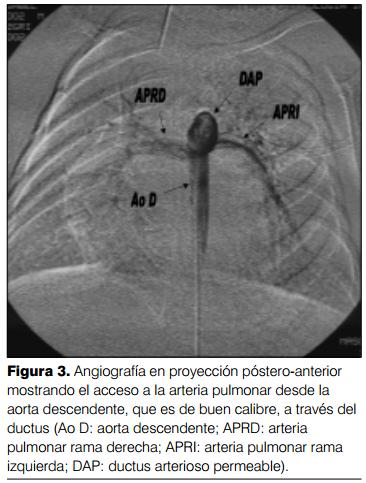

Cateterismo cardíaco (aortografía retrógrada) por vía arteria humeral derecha: a) interrupción del arco aórtico tipo A; b) ventana aortopulmonar tipo I, con importante cortocircuito de izquierda- derecha. Ductus arterioso permeable de pequeño calibre. Hipertensión arterial pulmonar a nivel sistémico con gradiente arteria pulmonar-ductus-aorta descendente de 30 mmHg. Dilatación de arteria pulmonar y cavidades izquierdas. FEVI normal (figuras 1, 2 y 3).